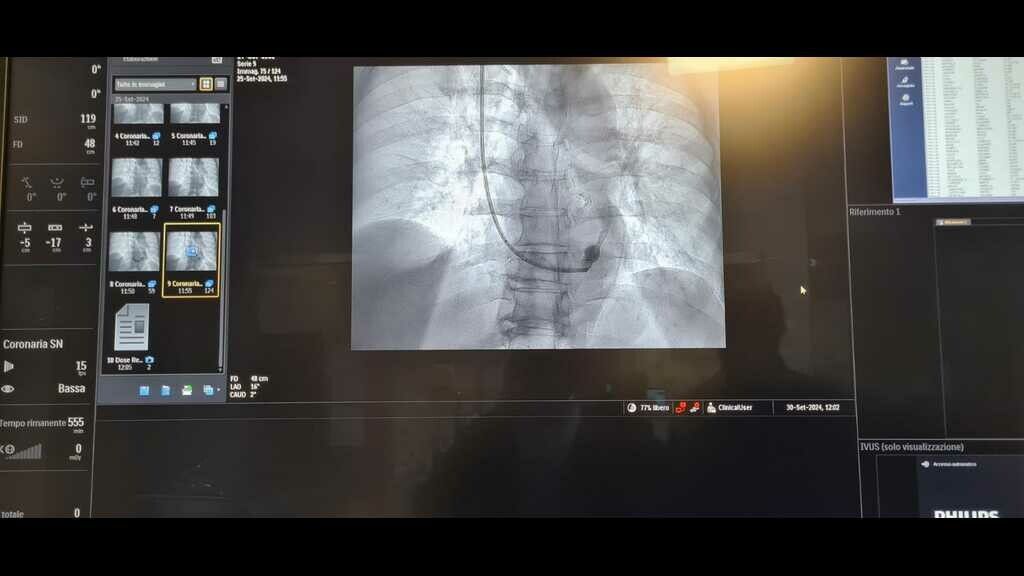

“Abbiamo eseguito questo intervento invasivo ma non chirurgico – ha spiegato Bonfantino - in un paziente di 63 anni, in anestesia locale, che è consistito nell’impianto di uno stent metallico (reducer), a forma di clessidra,  attraverso la vena giugulare, all’interno del seno coronarico, cioè la vena che sbocca nell’atrio destro del cuore e che drena tutto il sangue venoso di origine cardiaca, per poi raggiungere i polmoni ed essere ossigenato.  Questa procedura  - ha aggiunto -trova indicazione in quei pazienti coronaropatici sintomatici, che lamentano angina pectoris nonostante terapie farmacologiche ad alto dosaggio.  La presenza di tale sintomatologia, anche assumendo una terapia farmacologica ottimizzata, determina un aumentato rischio ischemico cardiaco e genera grande frustrazione per i pazienti che non sono quindi in grado di svolgere in serenità le normali attività quotidiane”.

L’impianto dello stent reducer in sala è stato coordinato dal dottor Maurizio Turturo, responsabile della UOS Emodinamica, e dal dottor Francesco Cassano. “Grazie alla particolare morfologia dello stent, a forma di clessidra – ha detto Turturo - si determina un rallentamento del drenaggio venoso cardiaco, permettendo la persistenza nel cuore di sangue ancora ossigenato e quindi il rilascio di una maggiore quantità di ossigeno al muscolo cardiaco. Ciò determina, in un’alta percentuale di casi, la risoluzione dei sintomi anginosi del paziente e il sensibile miglioramento della qualità di vita del paziente”.